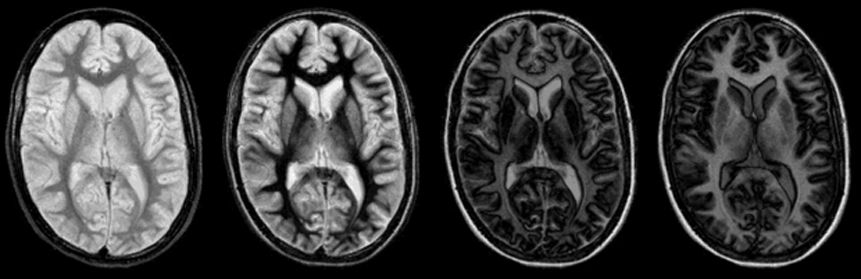

Figure 10-09:

The unexpected and abrupt contrast changes of an IR pulse sequence (cf. Figure 10-08): four images with increasing TI. One of the main problems (and advantages) of the IR sequence is that its con­trast be­ha­vi­or can change dramatically with only minimal changes of the inversion time.

Animation: In all images, TR = 4000 ms (different from the graph in Figure 10-08). TI from 100 ms to 2000 ms, increasing in steps of 100 ms.